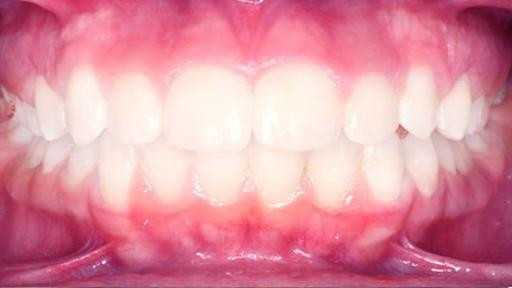

Установка сапфировых брекетов

Недоразвитие нижней челюсти, большой наклон передних зубов. Срок лечения 2 года. Сапфировые брекеты.

Доктор: Хачатрян Лариса Рубеновна